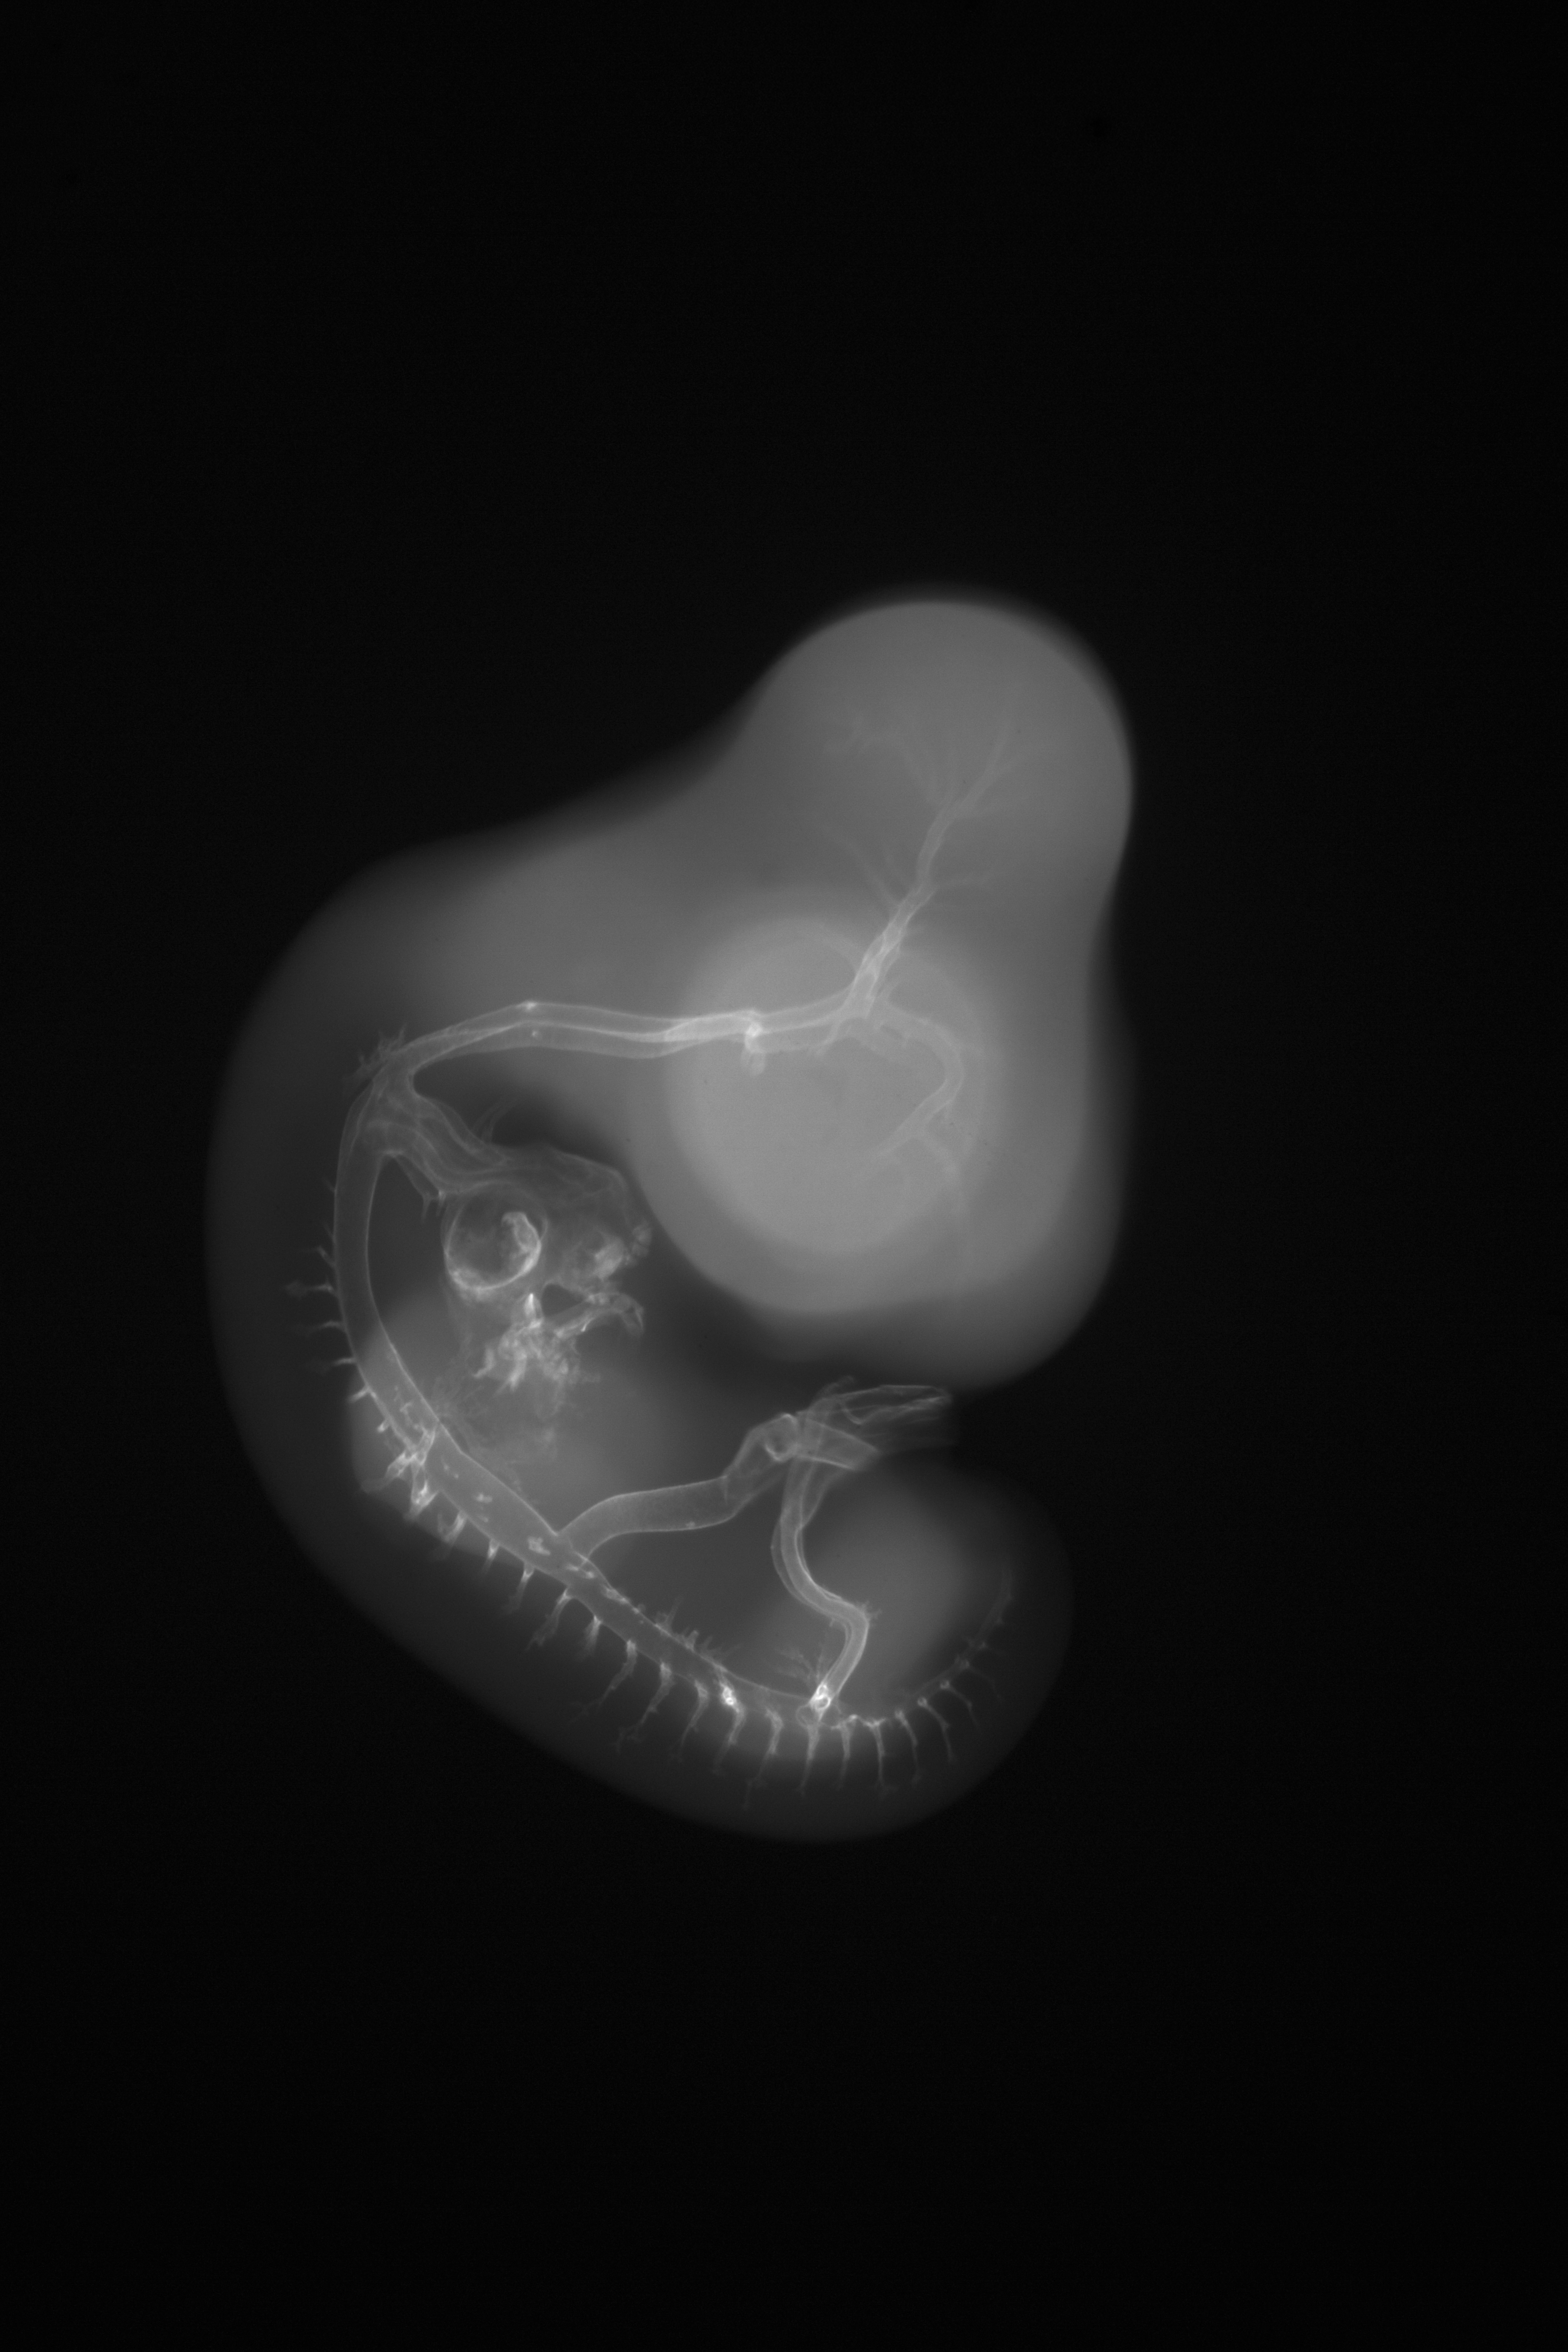

Hamburger-Hamilton (HH) Stage 26 (approx. 5 days)

X-Ray Micrographs